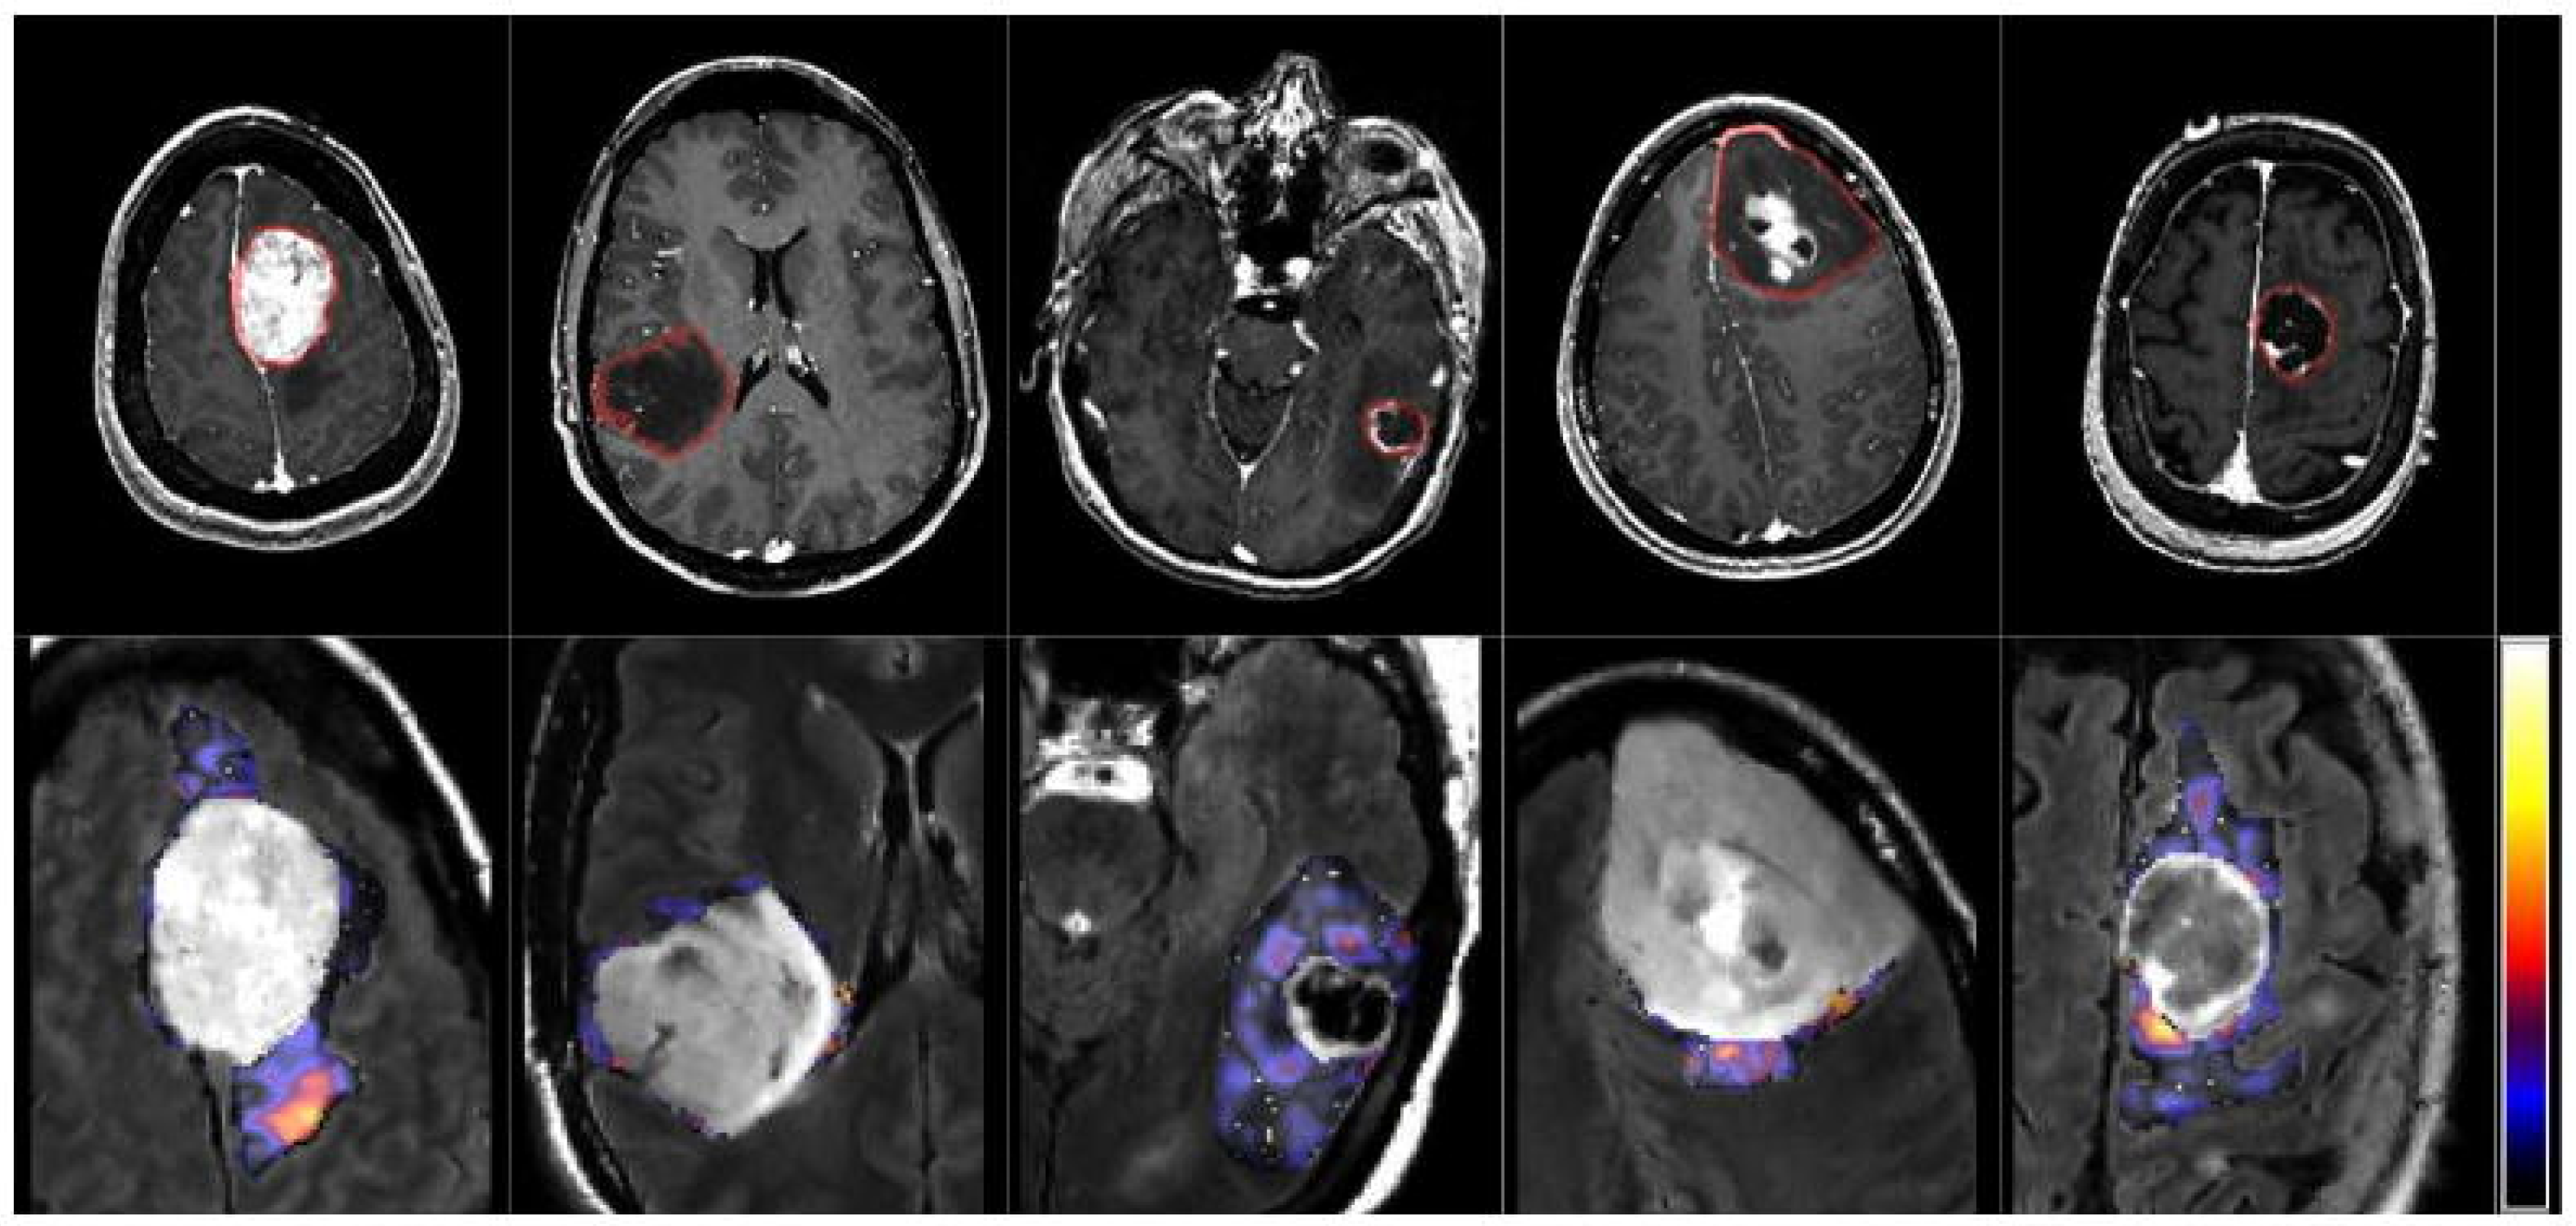

Figure 2. From left to right: meningioma, glioma grade II, grade III, grade IV and metastasis.

Figure 3. Sample scans from testing dataset.